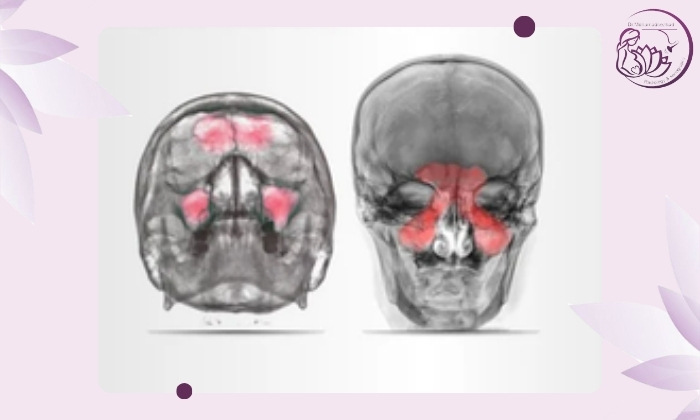

در عکس معمولی سینوسها میتوان تغییرات کلی زیر را تشخیص داد:

کدر شدن سینوسها: نشاندهنده وجود ترشحات یا التهاب.

سطح مایع (Air-fluid level): علامتی از عفونت حاد.

ضخیم شدن مخاط: از نشانههای التهاب مخاطی سینوسها.

از بین رفتن شفافیت هوا در سینوس: احتمال وجود سینوزیت خفیف یا مزمن.